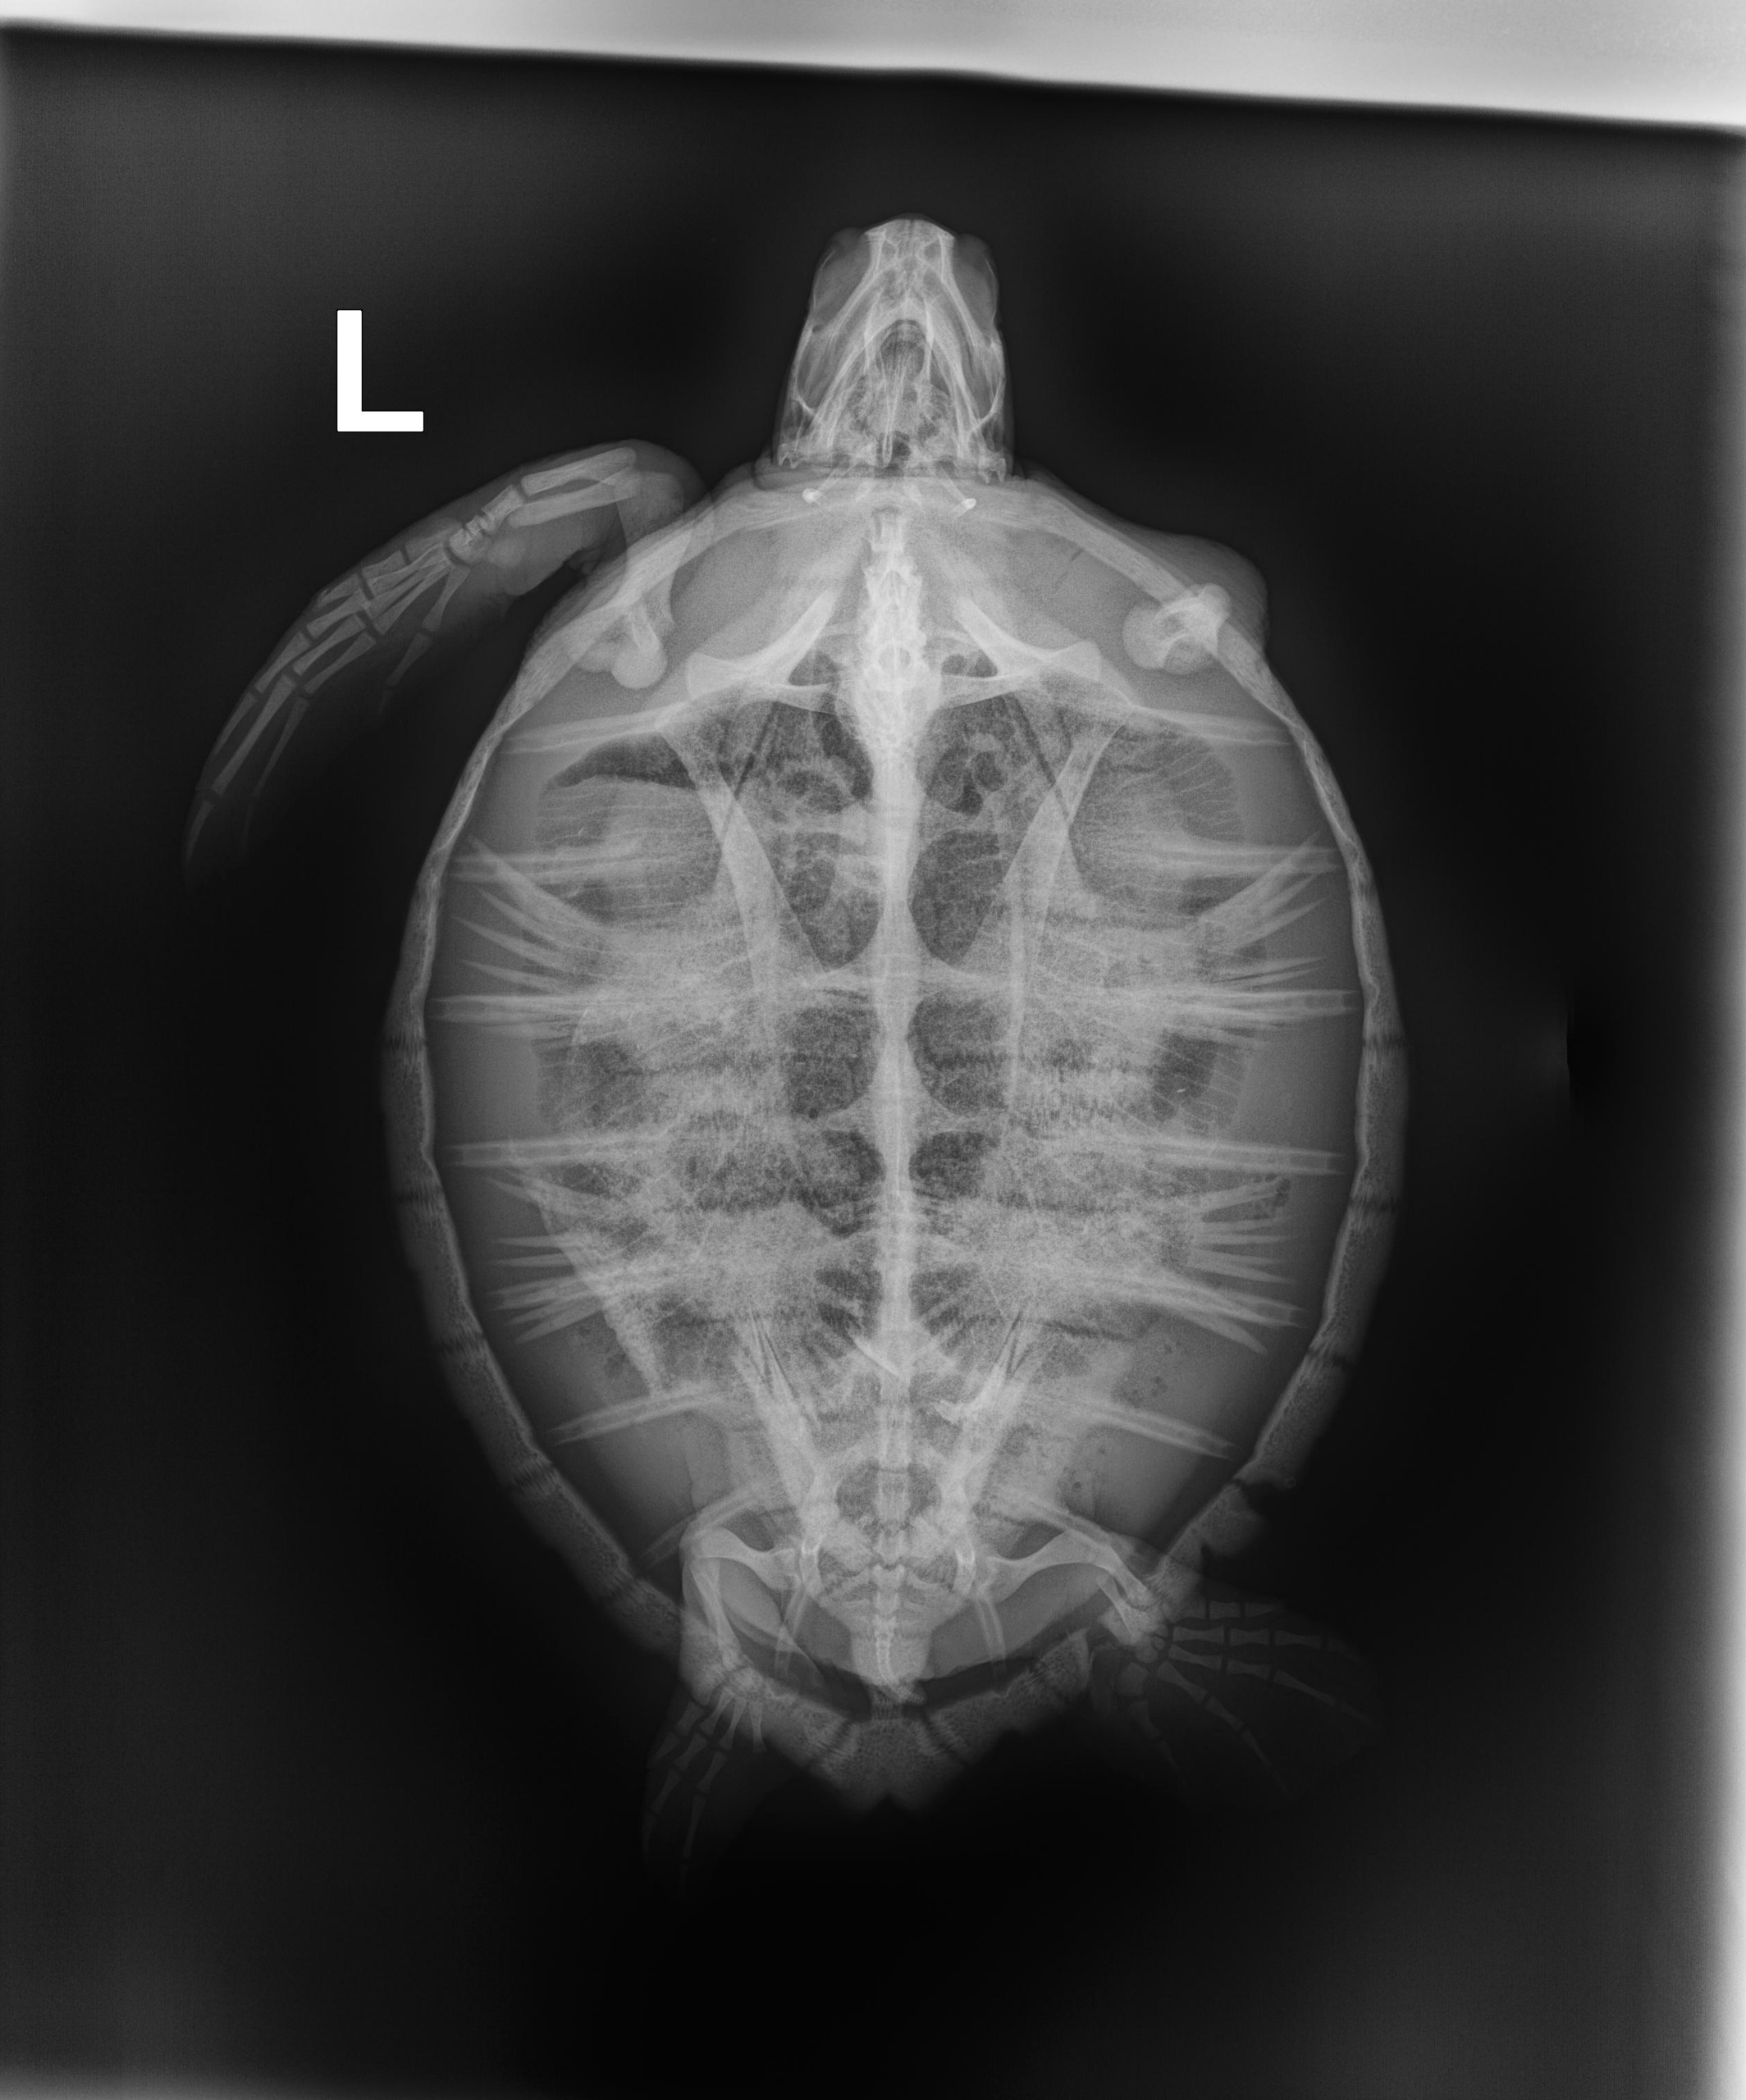

4.7 lbs. non-FP juvenile green

Missing right front flipper and a chunk out of left rear flipper (old injuries) minor abrasions and bruising on carapace and plastron.